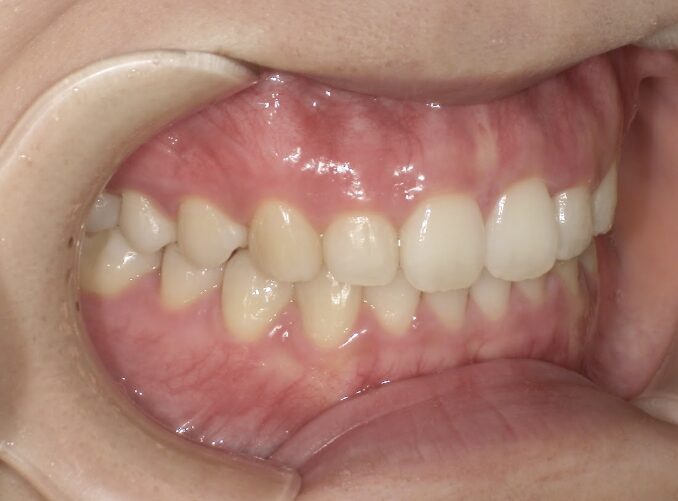

治療後

前歯のすき間が気になるを主訴に当院を受診され、前歯部空隙歯列(歯と歯の間に隙間が空いている状態)・過蓋咬合(上の歯が下の歯を深く覆いかぶさっている状態)・下顎前歯叢生(ガタガタ)を認めました。

IPRを使用してマウスピース型矯正装置(インビザライン)を使用し過蓋咬合及び叢生の改善を行いました。